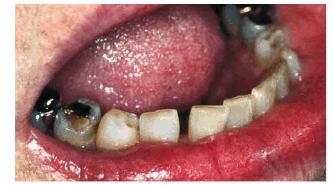

Figur 323s1823d e 18-2A: This teenager chipped her maxillary front teeth.

Figur 323s1823d e 18-2B: The left central incisor was bonded with composite resin.